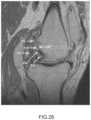

FIG.8 is a sagittal plane image slice depicting automatically generated slice curves of a femur and a tibia.